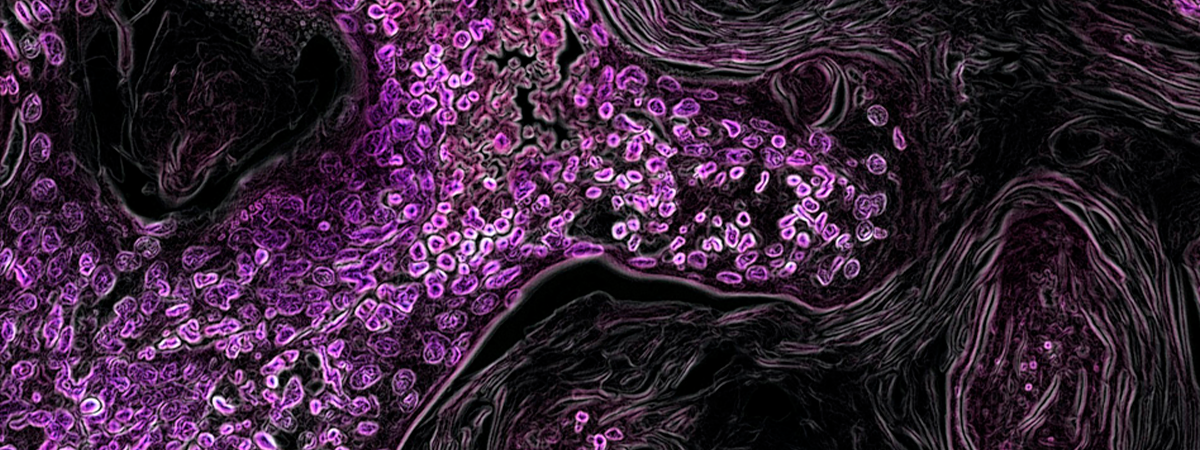

La oncología de precisión avanza en España, pero hay margen de mejora

A finales de octubre, la Sociedad Española de Oncología Médica (SEOM) presentó el primer informe sobre Implantación y regulación de la Oncología de Precisión en España , que realiza una radiografía de la situación actual y establece un decálogo de recomendaciones para mejorar el acceso en todo el territorio.